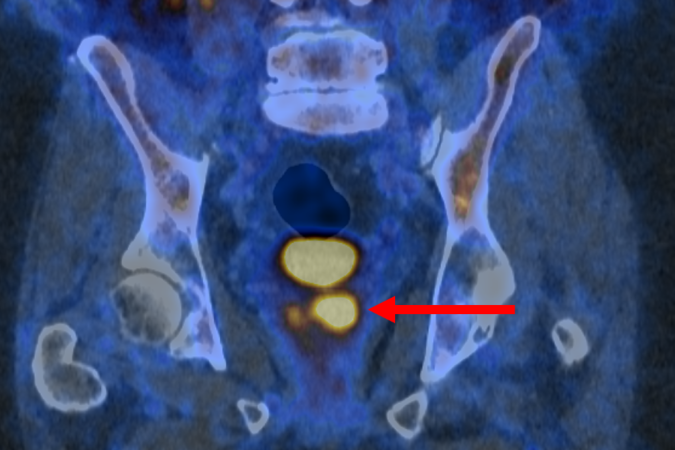

O exame PET/CT (tomografia por emissão de Pósitrons/tomografia computadorizada) com PSMA identifica células agressivas presentes na próstata, que são potencialmente prejudiciais e podem precisar de tratamento. Isso é possível graças a uma molécula que se liga a essas estruturas e as faz brilhar, aparecendo como pontos luminosos na imagem. O estudo afirma que isso também pode ajudar a reduzir o risco de sobrediagnóstico.

O ensaio descobriu que a tomografia por emissão de pósitrons (PET/CT) com PSMA podia identificar pessoas que não tinham câncer ou cujo tumor era de tão baixo risco e com crescimento tão lento que provavelmente nunca causaria danos. Esses pacientes não precisaram de biópsia. A nova abordagem reduziu pela metade o número de pessoas submetidas ao exame invasivo, sem deixar de detectar nenhum câncer maligno.

A abordagem também beneficiou os pacientes que ainda precisavam de biópsia. Os resultados da tomografia garantiram que o procedimento fosse direcionado às áreas suspeitas identificadas no exame de imagem, a fim de minimizar complicações e aumentar a precisão.